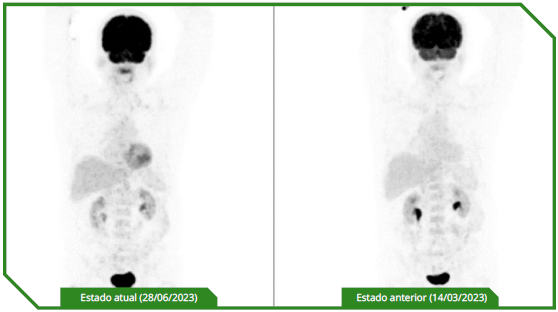

Paciente masculino de 65 anos, previamente sem comorbidades, diagnosticado com carcinoma espinocelular de língua, tratado inicialmente com cirurgia e radioterapia adjuvante, evoluindo precocemente com doença metastática pulmonar e óssea. No momento da avaliação oncológica, apresentava performance status comprometido e alta expressão de PD‑L1 (CPS 30). Optou-se por imunoterapia isolada em primeira linha, considerando perfil clínico e objetivo de redução de toxicidade, com acompanhamento longitudinal e intervenções locais conforme necessidade.